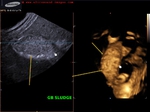

case-2: thick GB sludge causing hepatization of gallbladder- 3D ultrasound images

Sonography of the right hypochondrium shows a large distended gall bladder with markedly echogenic contents. The echogenicity appears similar to that of the liver (hepatization of the gall bladder). This ultrasound image suggests presence of limy bile in the gall bladder. This is caused by the collection of calcium rich salts within the organ and is an extreme form of biliary sludge. It is also known as Milk-of-calcium bile and is often associated with cholecystitis. Ultrasound image (upper most row- case-1) is courtesy of Prasenjeet Singh, MD, India. This image was taken using a Toshiba Nemio -30 system.

case-2: shows hepatization of gallbladder. Using a Samsung Accuvix ultrasound system.